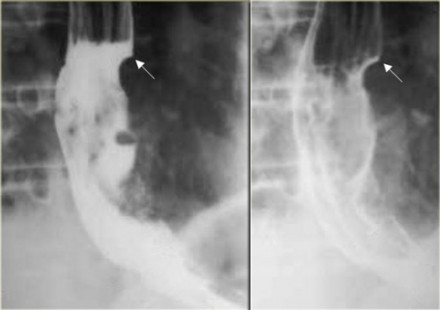

- рентгенографию с применением контрастного раствора;